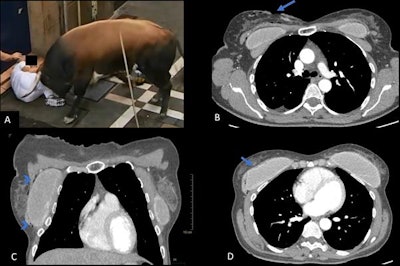

A: A 42-year-old man gored in the right side of the chest wall. B: Coronal view shows a pulmonary contusion (arrow) and subcutaneous emphysema (arrowheads). There is no pneumothorax. C: Axial view shows the entrance wound (arrow). D: Image from 3D VRT scan shows a displaced fracture of the 10th right rib and a nondisplaced fracture of the 12th left rib.The medical team at Navarra Hospital in Pamplona usually receives all the information on patients before they are admitted to the emergency department. Many doctors and nurses watch the spectacle on TV, so they know how patients are injured.